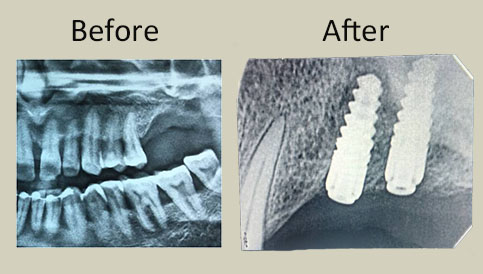

Images of cases done with prp

SINUS LIFT PROCEDURE FOR IMPLANT PLACEMENT